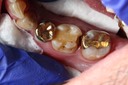

Alan Chinn #31 pre-op

Alan Chinn #31 caries removal

Alan Chinn #31 prep

Alan Chinn #31 model

Alan Chinn #31 finish